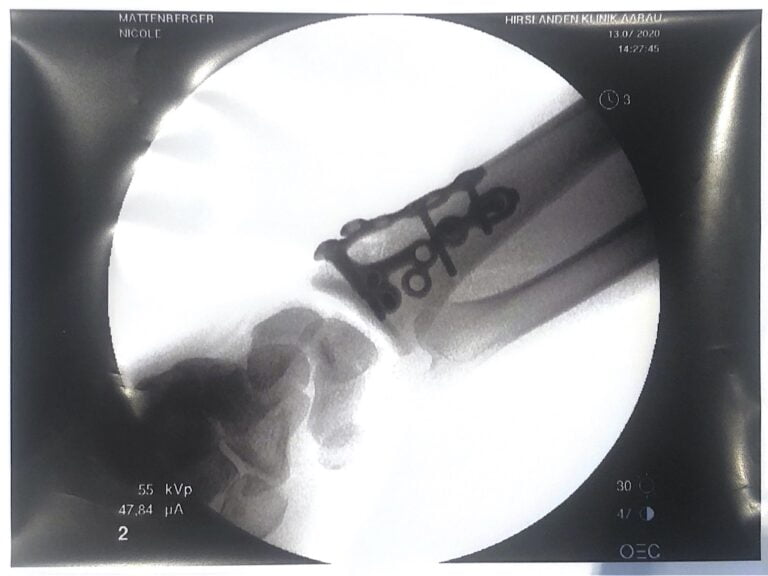

When we were looking for a resting place for lunch after 20km in Waltenschwil, Nicole fell while getting off the bike because she couldn’t get out of the click pedals and broke her forearm on the first day. We had to drive back home by public transport and the next day she had the operation under general anesthesia.